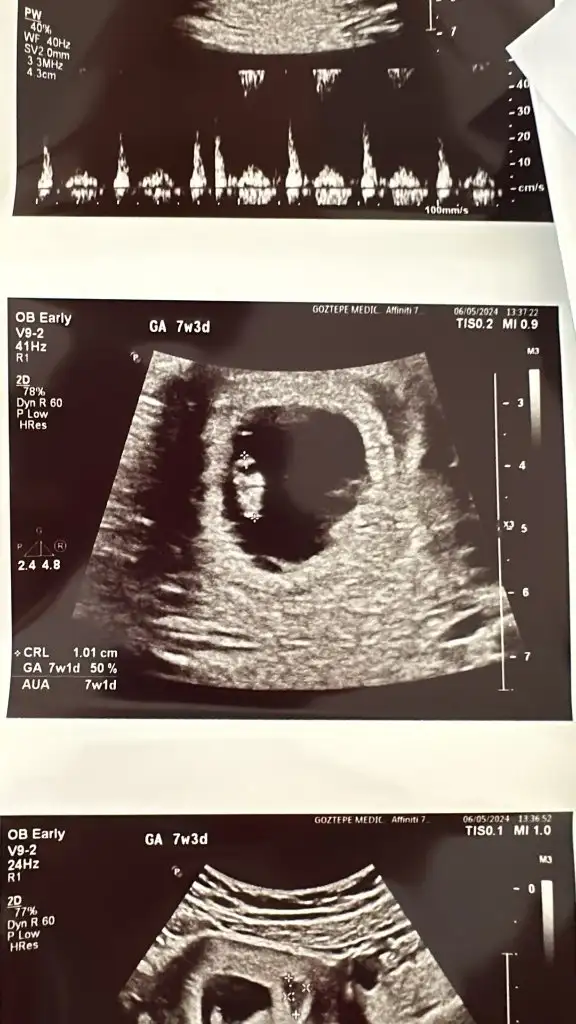

Eki Görüntüle 3425161